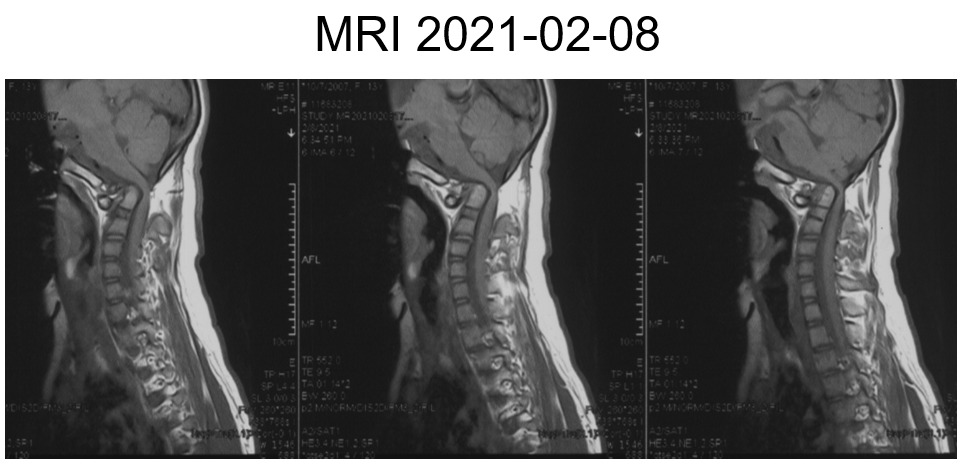

女,13岁,154cm,57kg

• 6个月前病人出现颈部活动受限,3个月前出现左手力弱

影像资料:

• 齿状突小体

• 寰枢椎脱位